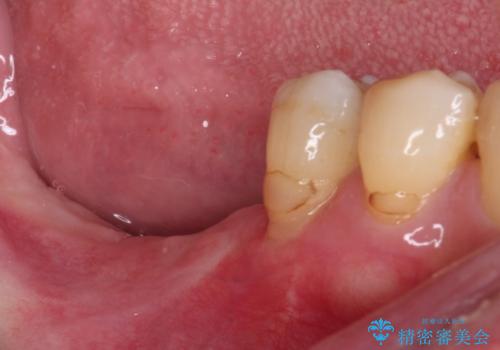

- 60歳を越え、黄ばんだ前歯をセラミッククラウンできれいな口元にしたいとのことで来院された患者様です。

診察したところ、前歯は反対咬合であり、その影響で抜歯が必要な奥歯があることが分かりました。

抜歯が必要な奥歯は、インプラント並びにブリッジにより補綴を行い、上下前歯は反対咬合を改善させるように補綴治療を行うこととしました。